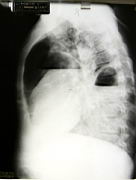

This patient has both a pulmonary abscess and an empyema at the same time! |

Lateral view, same patient |